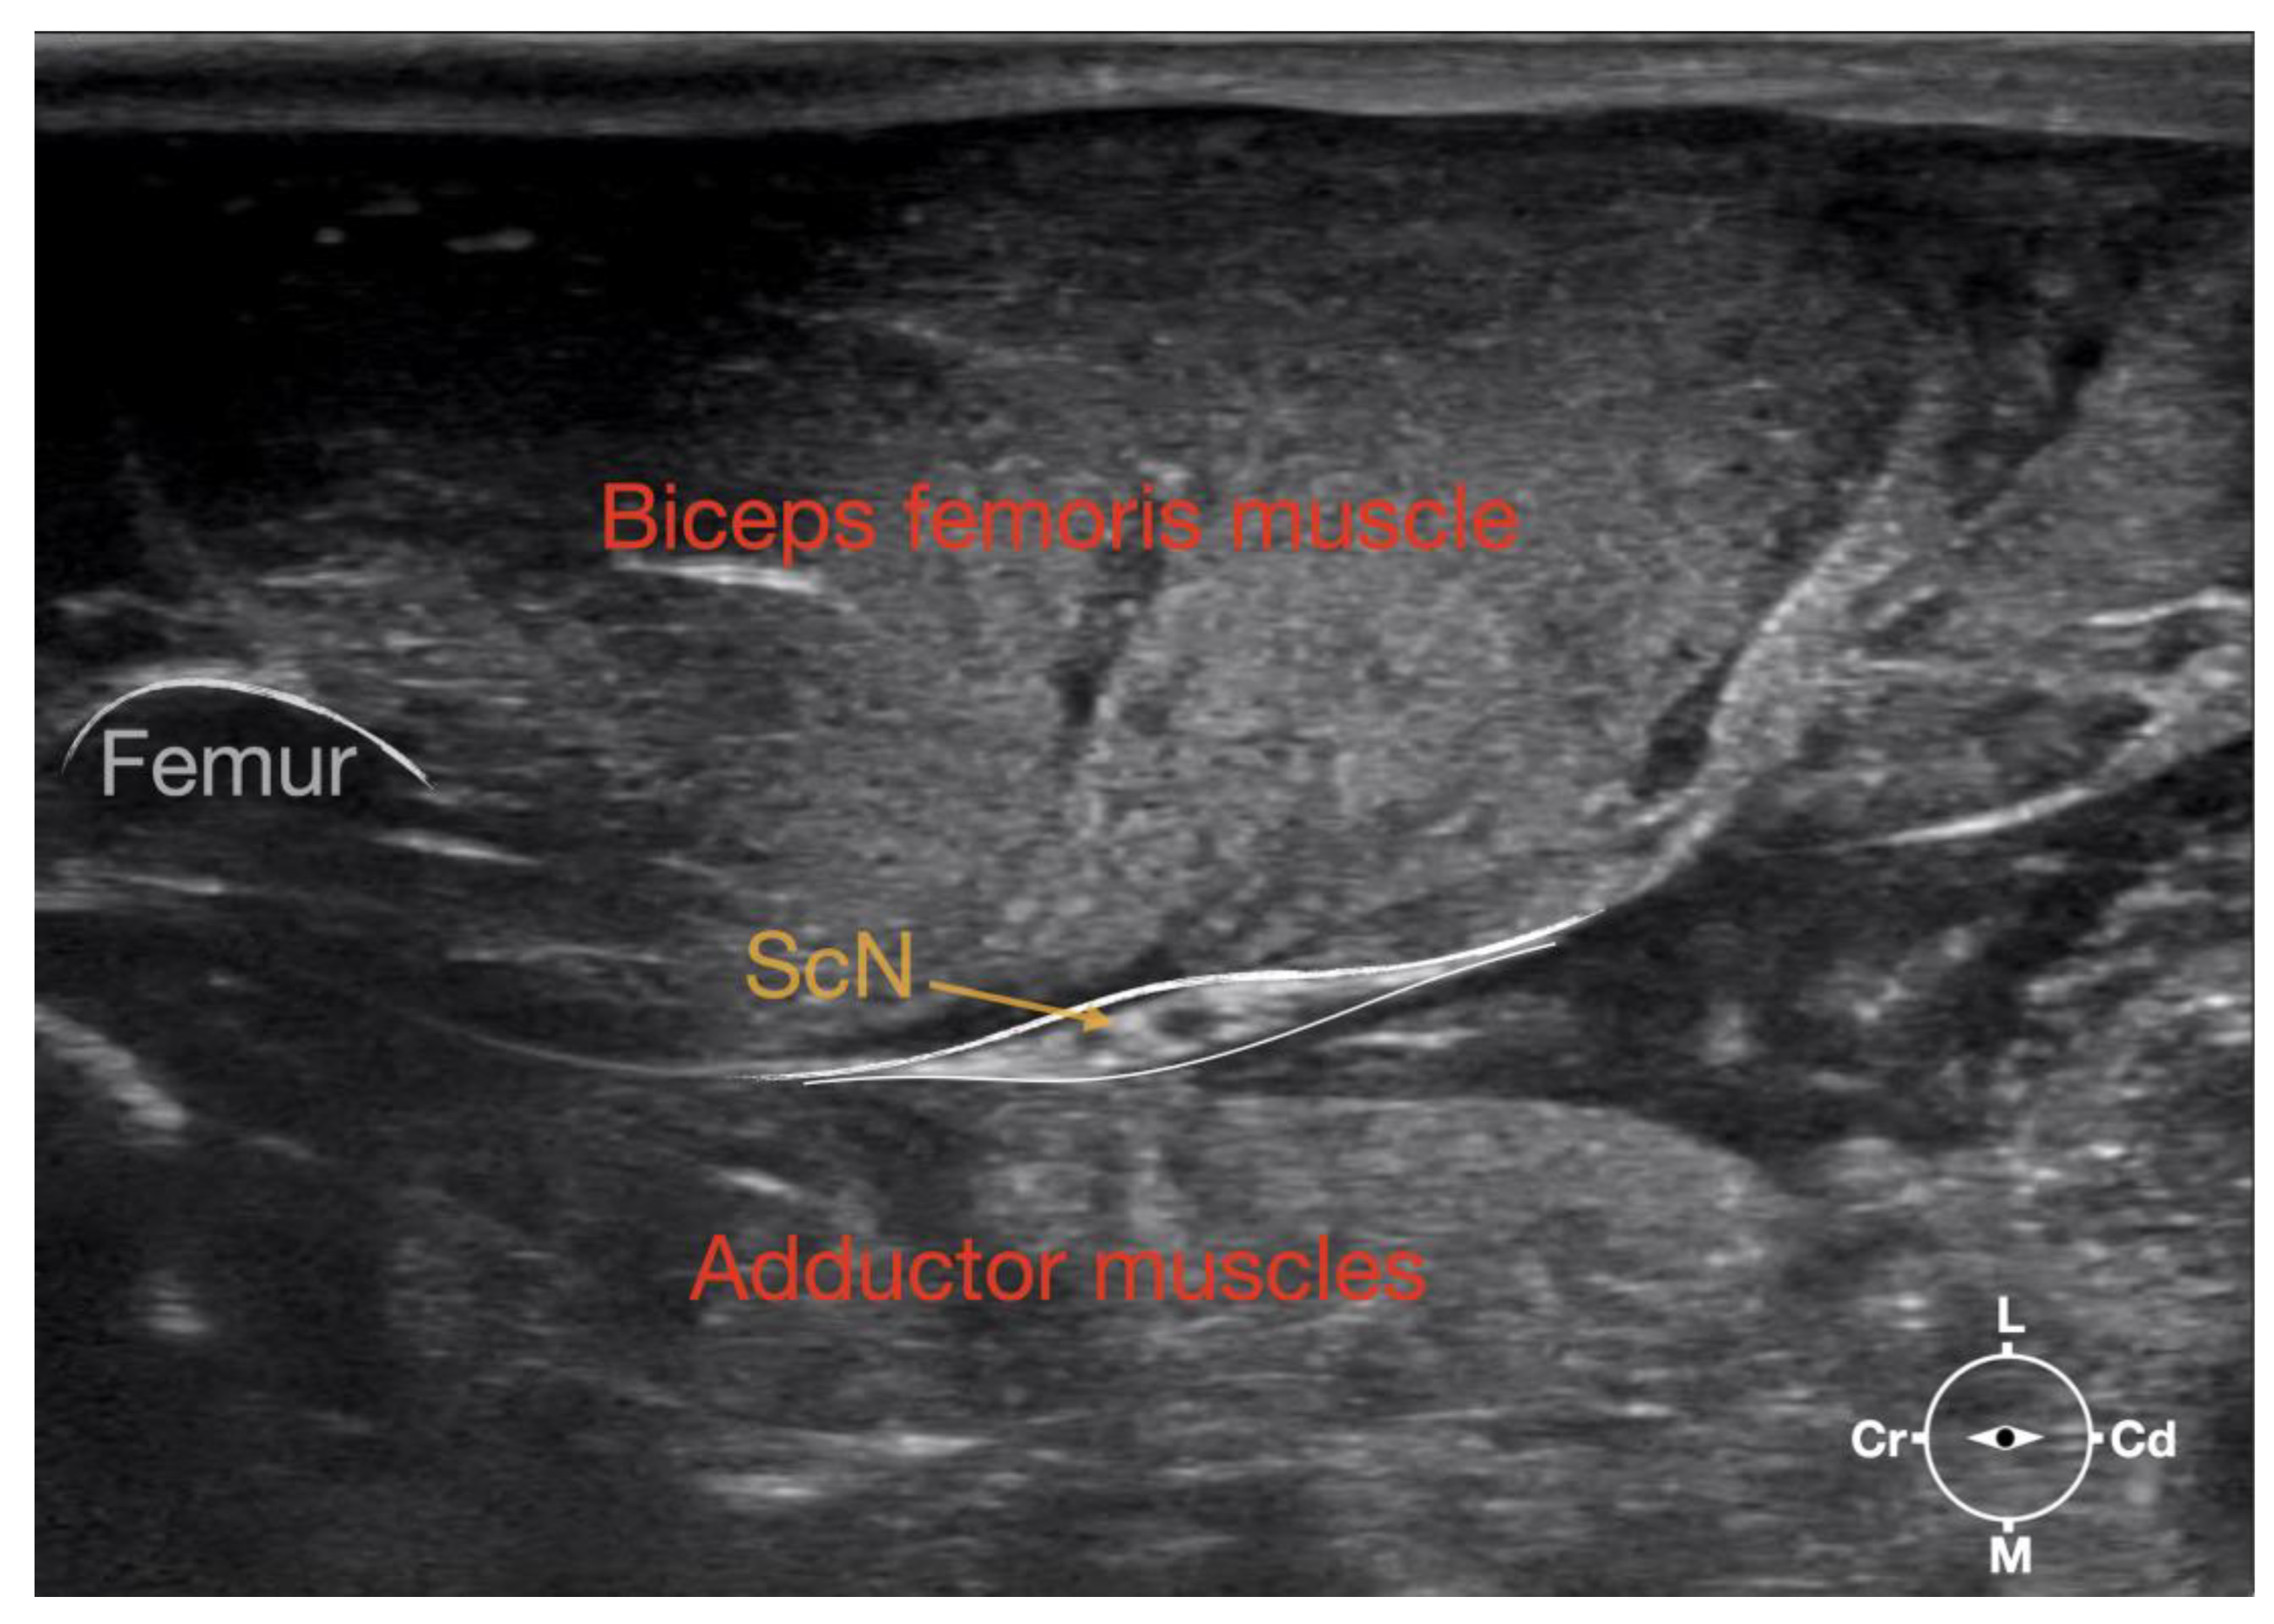

Figure 3. Ultrasonographic image showing the approach of the needle towards the sciatic nerve. ScN, sciatic nerve; Cr, cranial; Cd, caudal; L, lateral; M, medial.

Ultrasonographically, the sciatic nerve appeared as a binocular structure with a hyperechoic rim surrounded by the muscular fascias of the biceps femoris and adductor muscles at this level. All muscles were displayed as structures with heterogeneous echogenicity. The biceps femoris muscle was lying lateral to the ScN while the adductor muscle was medial to the ScN. The femur was displayed as a hyperechoic structure with acoustic shadow and located cranial to the ScN nerve.